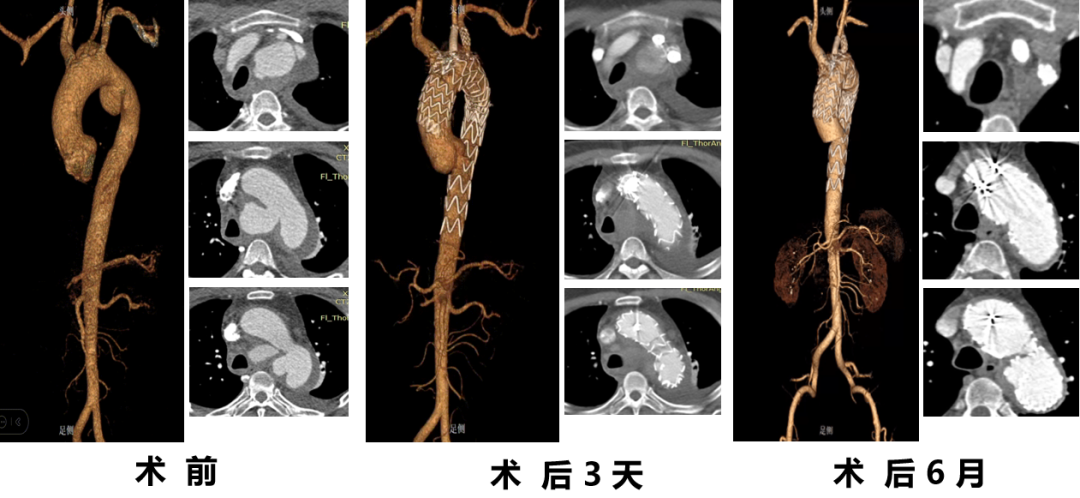

顾某,男,50岁,“胸背部疼痛3天”入院,主动脉CTA提示:主动脉夹层(多发性主动脉弓部溃疡);2.降主动脉假性动脉瘤;3.主动脉壁内血肿(B型)。

术前CTA

术前造影

术后造影

手术用时140分钟